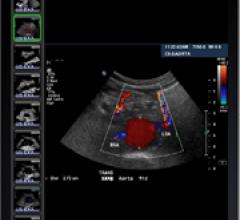

December 20, 2010 – PET CT fusion software is now available on a Web-based viewer. Medweb’s software can be used with its Web-based teleradiology and telemedicine applications. Historically, fusion software has been available only on dedicated workstations for nuclear imaging. With the software, users can fuse CT and PET images from any desktop computer using Internet Explorer.